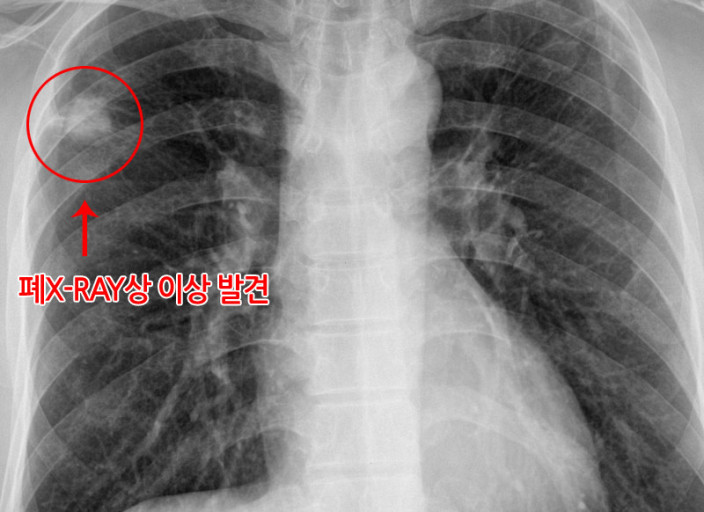

초기 폐렴의 가장 흔한 증상 중 하나는 기침입니다. 기침은 보통 건조하거나 가래가 섞여 있을 수 있습니다. 가래의 색은 처음에는 투명하다가 시간이 지나면서 노란색 또는 초록색으로 변할 수 있으며, 이는 염증이나 감염이 진행되고 있다는 신호일 수 있습니다.

폐렴에 걸리면 폐가 염증으로 인해 제대로 기능하지 못하게 되므로 호흡이 어려워질 수 있습니다. 특히 가벼운 활동 후에도 숨이 차거나, 심한 경우에는 편안히 앉아 있어도 호흡이 힘들어질 수 있습니다.

폐렴에 걸리면 가슴에 통증을 느끼기도 합니다. 이 통증은 깊은 숨을 들이마시거나 기침을 할 때 더욱 심해질 수 있습니다. 폐에 염증이 생기면서 가슴 부위에 불편한 느낌이나 날카로운 통증이 동반될 수 있습니다.